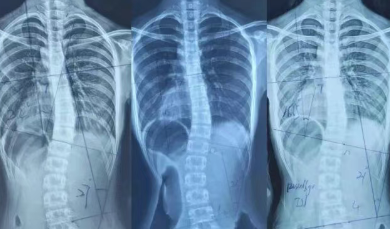

从叶天士辛润通络法论治强直性脊柱炎侯珺婷,韦 尼 强直性脊柱炎(AS)是一种慢性中轴脊柱炎症性疾病,主要侵犯脊柱与骶髂关节。AS好发于青壮年,流行病学调查显示,AS发病呈现出明显家族聚集倾向。AS属中医学“大偻”“竹节风”“肾痹”范畴。目前认为,AS是在先天不足的内因作用下,风、寒、湿、痰..

一、病因病机1.1 感受外邪1.2 肾督亏虚1.3 血瘀气滞二、诊断要点三、辨证论治3.1 邪实候3.2 正虚候3.3 痰瘀候四、预防与护理五、结 语脊痹是以脊部疼痛、僵硬、沉重,甚至强直为主要表现的风湿病。脊痹为肢体痹之一..